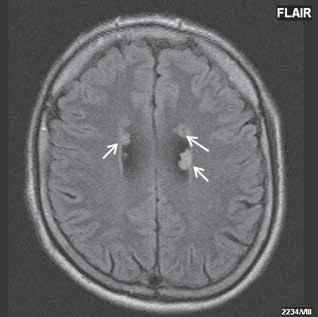

I 5 2 „Fyziologická“ ložiska zvýšeného signálu v T2W obrazu v bílé hmotě mozkové 187

Roztroušená skleróza (RS) 189